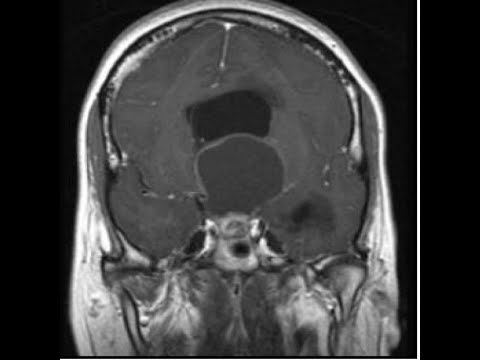

relação íntima com a hipófise a neuro-hipófise sendo uma continuação do infundíbulo hipotálamo e o exame de imagem na ressonância e se nós tomamos o corte sagital exatamente na linha média nós podemos observar aqui e o assoalho do terceiro ventrículo correspondendo ao encontrar a botar aqui um fundinho bruce continuando para compor a neuro impostos e eu vejo que há tumores que se desenvolvem nessa região é um tumor que afeta a região do hipotálamo é o craniofaringioma e foi assunto da minha tese de doutorado fiz pesquisa genética do crânio faringe oma tentando ajudar a obter mais meios

veja na imagem esse craniofaringioma uma porção sólida aqui na cela uma porção cística migrando para cima e acertou derrotarmos sem dúvida comprimido o seu plano provocando aí e no paciente assim não importa alegre é um s10 em algumas funções e estes eram alguns aspectos que nós gostaríamos de discutir de um modo bastante básico e objetivo sobre potara mas que já introduz a compreensão sobre a sua estrutura e a sua função espero que tenham aproveitar ficamos à disposição nos olhos meios de contato que é estão e até uma próxima oportunidade